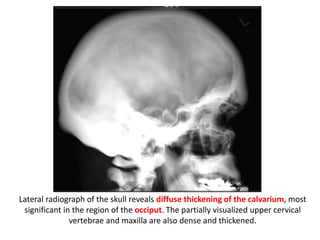

Lateral radiograph of the skull reveals diffuse thickening of the calvarium, most

significant in the region of the occiput. The partially visualized upper cervical

vertebrae and maxilla are also dense and thickened.

Lateral radiograph ofthe skull reveals diffuse thickening of the calvarium, most significant in the region of the occiput. The partially visualized upper cervical vertebrae and maxilla are also dense and thickened.